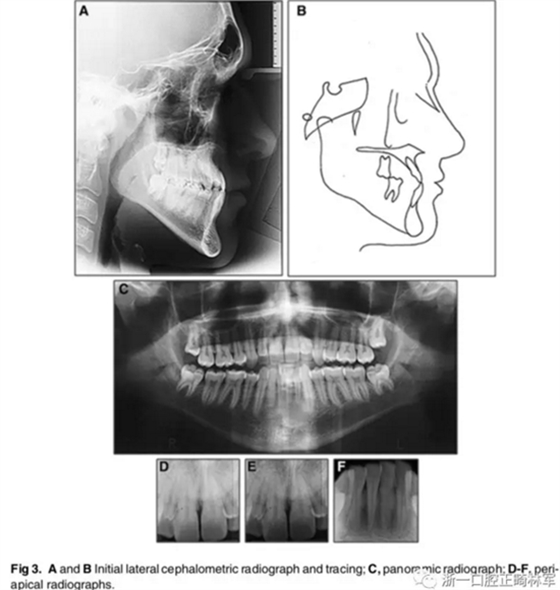

影像檢查:

X片示:III類(lèi)頜骨關(guān)系(ANB,-4°;Wits值,-10mm);上切牙前突、唇傾,下切牙內(nèi)縮(1:NA, 8mm、35°; 1:NB, 4mm、15°;IMPA, 77°);綜合考慮咬合平面角、下頜平面角、Y軸角,判定為水平生長(zhǎng)型;McNamara分析示,上頜相對(duì)顱底后縮(Co-A, 88mm; A-NPerp, 4mm),下頜相對(duì)顱底前突(Co-Gn, 135mm; Pog-Nperp, 10mm),上下頜骨不調(diào)(Co-A–Co-Gn, 47mm);此外,患者4個(gè)第一前磨牙缺失。